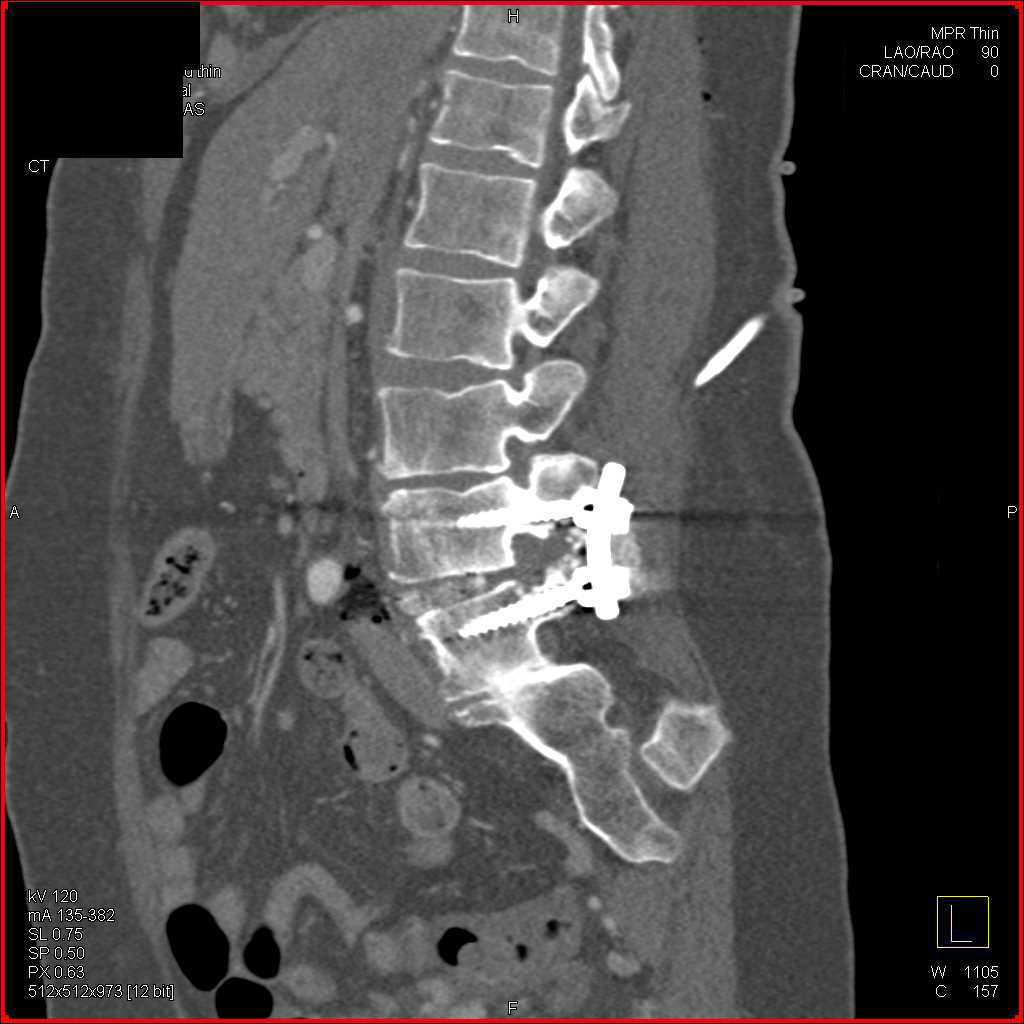

Multiple Exostosis Scapula and Humerus